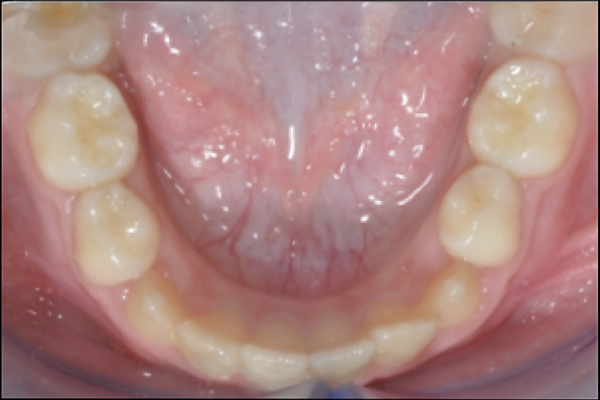

Morso inverso anteriore

Il morso inverso o morso crociato anteriore rappresenta una condizione in cui i denti superiori chiudono all’ interno dei denti inferiori (al contrario di come dovrebbe essere) ed è spesso sintomo di un problema scheletrico più importante chiamato malocclusione di III Classe. Questa caratteristica scheletrica, spesso ereditaria, richiede un trattamento precoce per il suo miglioramento. Pertanto i piccoli pazienti vanno visitati fin da subito senza aspettare il cambio dei dentini da latte, per assicurare un trattamento efficace e tempestivo. Diverse sono le apparecchiature che si possono utilizzare per ogni caso specifico, da quelle rimovibili a quelle fisse, e questo tipo di problema richiede spesso trattamenti in più fasi da rivalutare nel tempo durante la crescita.

PRIMA